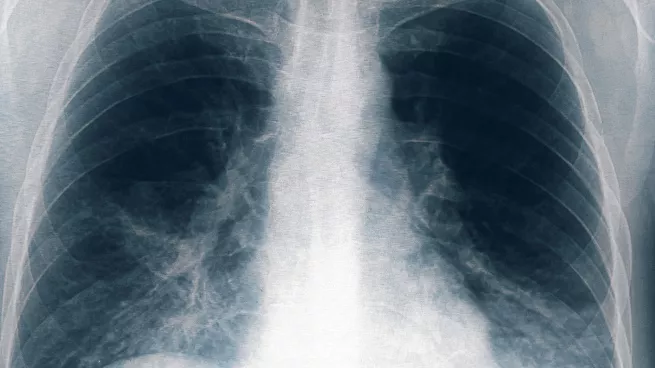

La Legionella, conocida también como Enfermedad del Legionario, es un tipo de neumonía grave, una infección en los pulmones.

Según el Centro Nacional de Inmunización y Enfermedades Respiratorias (NCIRD), la bacteria Legionella puede causar un tipo grave de neumonía (infección de los pulmones) llamada enfermedad del legionario.